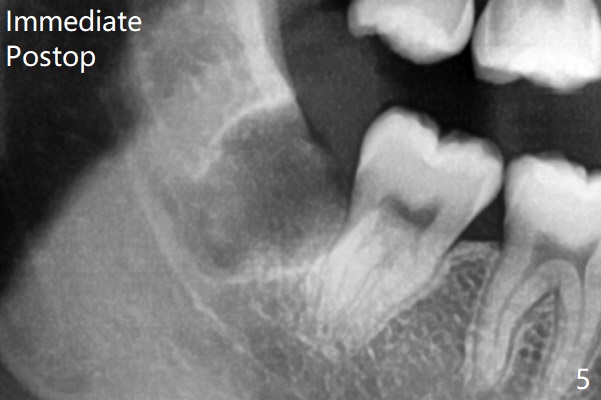

Extraction of #32 is easy, relative to #1 (Fig.5 (collagen plug placed)). There is no communication with the Inferior Alveolar Canal intraoperatively. #32 overlaps with #31, but incision is not placed mesial enough.